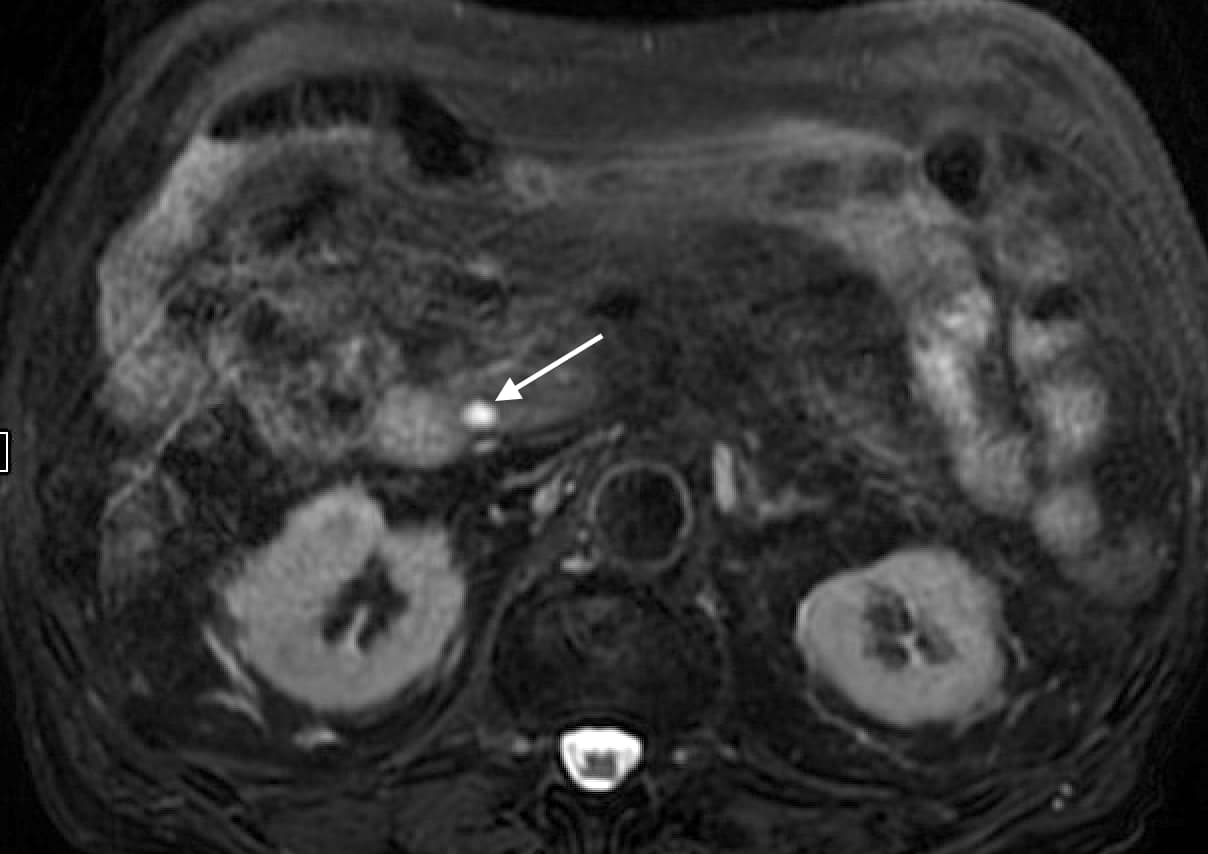

MRI:

- MRCP is the ideal investigation and will show cystic dilatation of biliary tree and relationship (and communication) of cysts with adjacent bile ducts.ย

- Hypointense on T1WI, hyperintense on T2WI, without wall enhancement on post-contrast images – Signal follows biliary tree.

- The presence of abnormal wall hyperenhancement or thickening can be due to superadded infection or malignancy (particularly with nodular or irregular wall thickening).